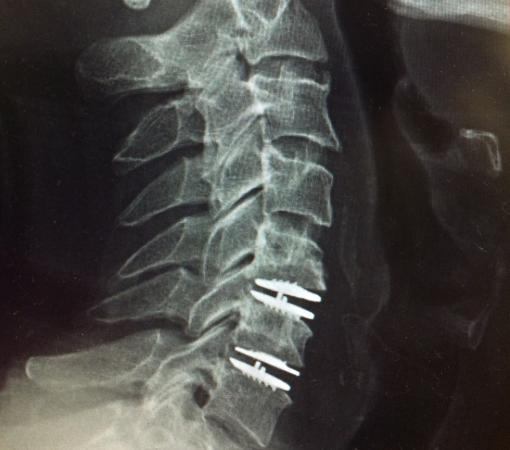

At Synapse Spine, the damaged disc is removed and replaced with an artificial one, helping restore spinal mobility. Disc replacement surgery in Mumbai ensures long-term relief from back pain.